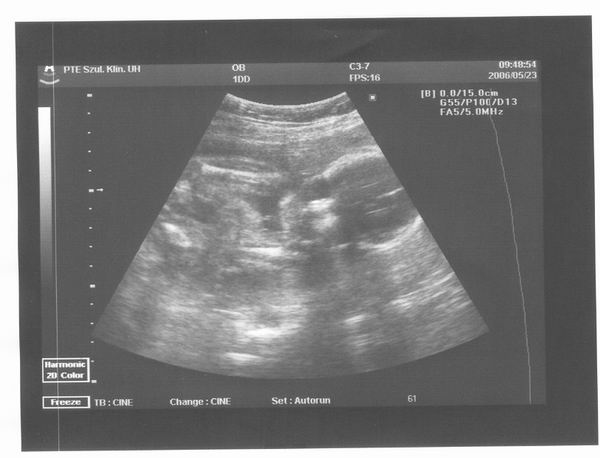

Akkor, íme Ficike sztárfotója:

Kép

Elvileg szemből látni a kobakját, a bal válla fel van húzva és a keze a pocija előtt. A jobb felkarja látszik még. A lábai már nem fértek a képre. :D Remélem, jól értelmeztem a képet :lol:

Június 9-én megyünk 4D UH-ra, már nagyon várom. Ott, gondolom, már jobban lehet majd látni.